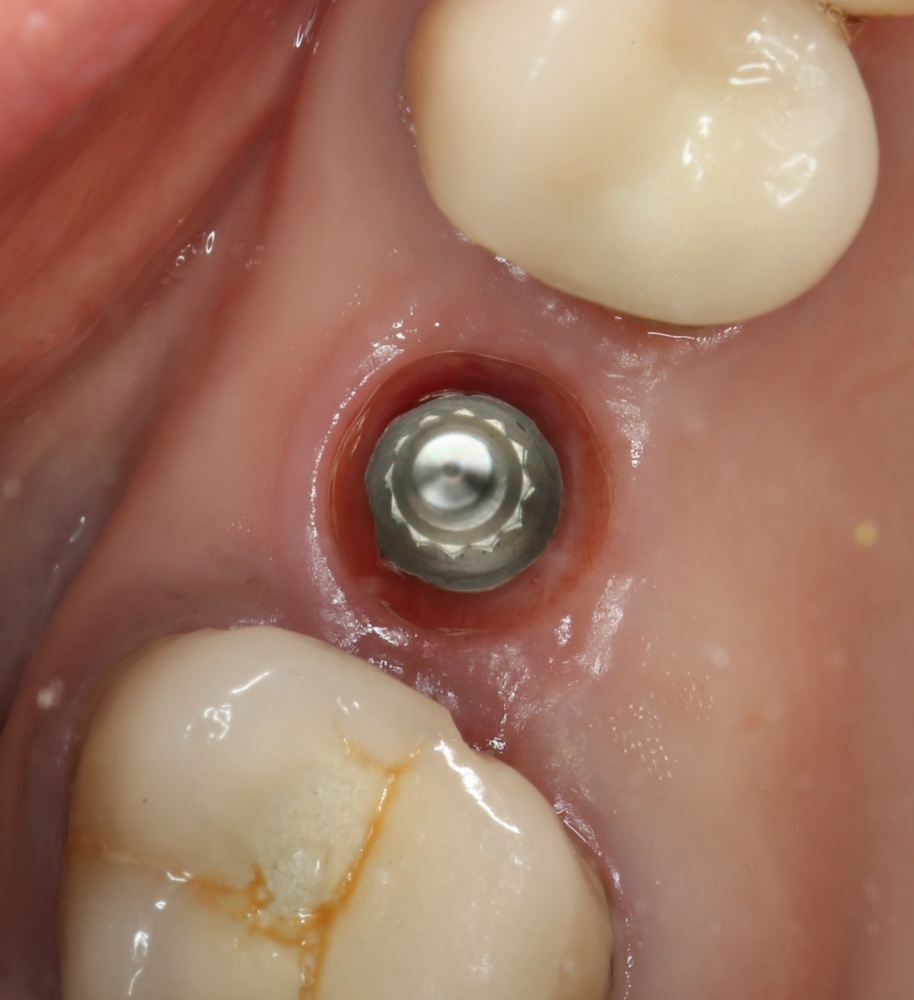

Но это еще не самое веселое. Допустим, мы решили проблему соединения «имплант-абатмент», у нас нет проблем с люфтами, а сам имплантат настолько хорошо интегрировался, что способен любую нагрузку в любом направлении. Возникает другая проблема — размер супраструктуры и соответствие ее нормальной биологической длине коронки зуба:

На фотографии выше, коронки опираются на обычные импланты, но даже в этом случае увеличение высоты супраструктуры усложняет гигиену и требует более пристального дальнейшего наблюдения. С ультракороткими имплантами, если честно, всё еще хуже.

Как будет выглядеть такая конструкция? Какой длины будут коронки? Возможно, на эстетику даже можно забить, ведь для некоторых людей красота зубов в боковом сегменте челюсти за пределами эстетически значимой зоны не так важна, но… как быть с уходом за протетической конструкцией и ежедневной гигиеной? Ведь, чем больше по размеру протез, тем сложнее за ним ухаживать. Тем больше мест, где может остаться зубной налет, а это, как вы понимаете, может привести к очень неприятным последствиям — периимплантиту, что для ультракоротких имплантов очень критично. А застревание пищи между протезом и десной? Можно ли назвать это «повышением качества жизни пациента»? Вряд ли.